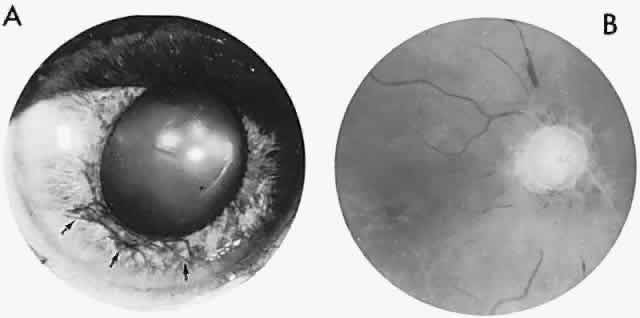

Fig. 7. Ocular hypoxia with subacute carotid occlusion. The patient complained of a painful red eye. A. Anterior segment shows an irregular, fixed pupil and iris rubeosis (arrows). B. Fundus demonstrates combined retinochoroidal infarction with acute excavation of the optic disc. Arteriography revealed right internal carotid occlusion.